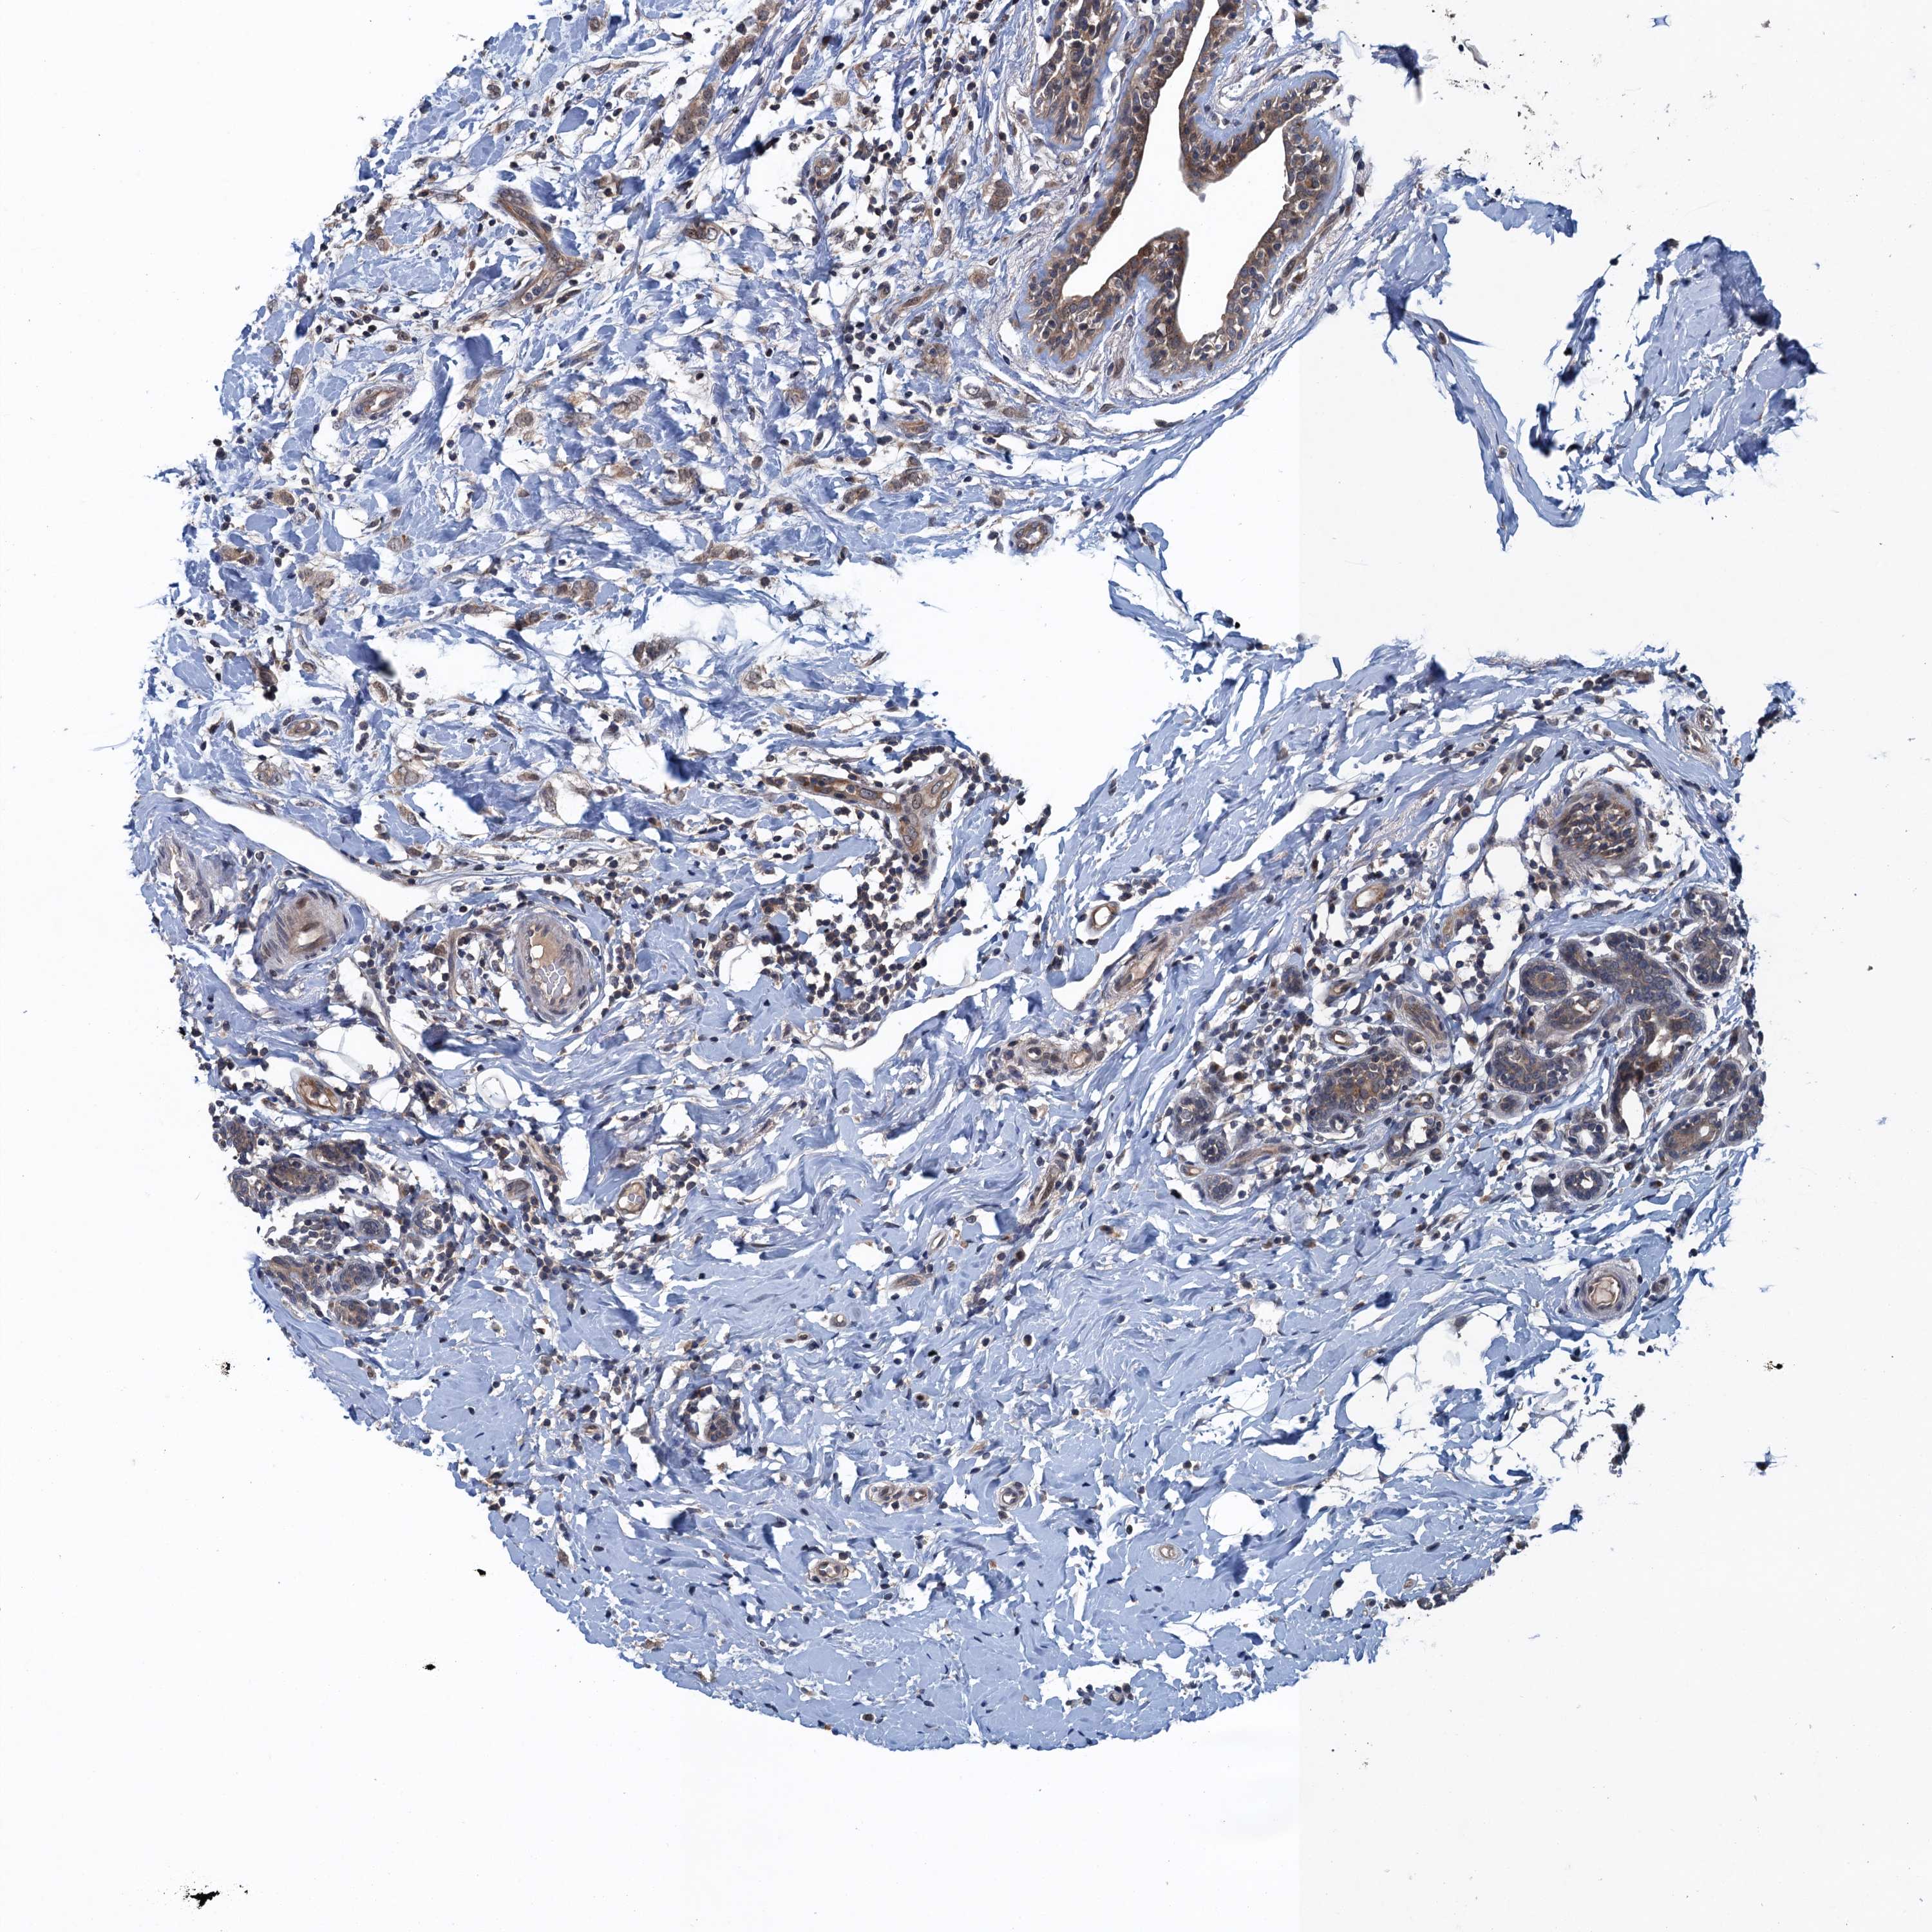

CANCER BREAST CANCER Show tissue menu

BRCA TCGA BRCA VALIDATION PROTEIN EXPRESSION